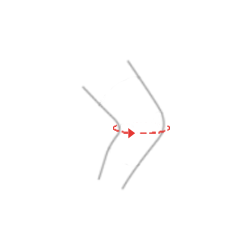

Szyny [2] – to dwuosiowe szyny policentryczne, wyposażone w mechanizm zębatkowy, których ruch zgięcia i wyprostu zbliżony jest do anatomicznego ruchu stawu kolanowego. Wykonane są z wysokiej jakości stopu aluminium pokrytego na gorąco trwałą powłoką proszkową, co powoduje że są one obojętne na działanie potu pacjenta i zawartej w nim soli. Szyny posiadają specjalnie ukształtowany wkład silikonowy, który stabilizuje szynę na kończynie pacjenta i dodatkowo odciąża staw kolanowy.![Szyny [2] Szyny [2]](http://reh4mat.com/uploads/2012/09/szyna_2_czarna_sch.png)